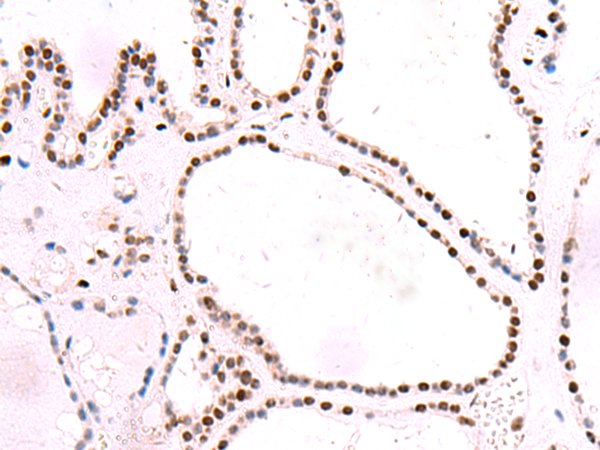

分类: 科研抗体货号: P10144别名: RSE1; SAP130; SF3b130; STAF130应用: IHC反应种属: Human, Mouse